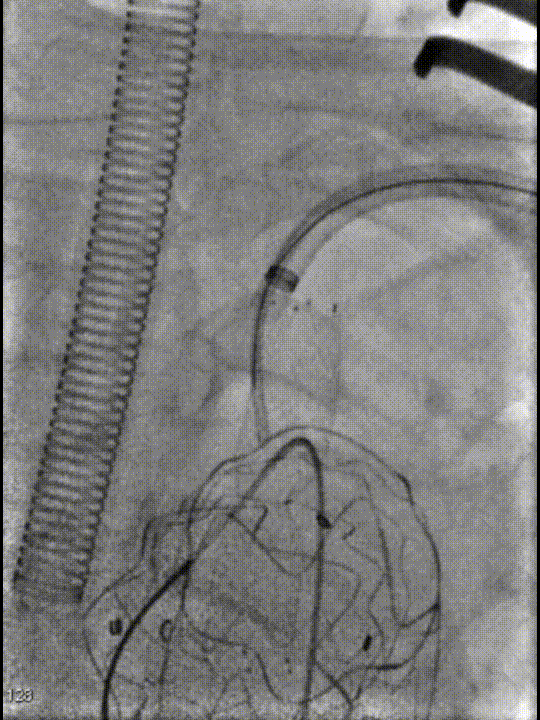

从预先切开好的左侧颈总动脉穿刺送入6f动脉鞘,将鞘头顶在覆膜支架上,使用asahi treasure 12导丝顺利突破覆膜区。

先后导入4mm、6mm和8mm球囊对覆膜区进行扩张。考虑到患者颈总动脉存在较严重的动脉硬化,为避免置入大血管鞘带来的风险,选择使用10-40mm自膨式裸支架重建左颈总动脉,使用10-60mm球囊进行后扩张。扩张后,支架形态满意,成功恢复了左侧颈总动脉血流。

图1

图2

图3

更换MUSTANG 8-40mm球囊进一步扩张开窗处(图2)